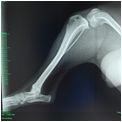

Für chirurgische Eingriffe, die bei uns nicht durchgeführt werden können, (z.B. Knochen- und Wirbelsäulenchirurgie) empfehlen wir Ihnen nach vollständiger Diagnostik uns vertraute, bewährte Spezialisten.

Im Falle einer Überweisung wird der Kollege von uns mit sämtlichen Befunden (z.B. digitale Röntgenbilder auf CD oder per E-Mail) versorgt, so daß ohne Zeitverzögerung behandelt werden kann. Die Nachbehandlungen erfolgen dann in der Regel wieder in unserer Praxis, um Transportstress und Aufwand zu minimieren.